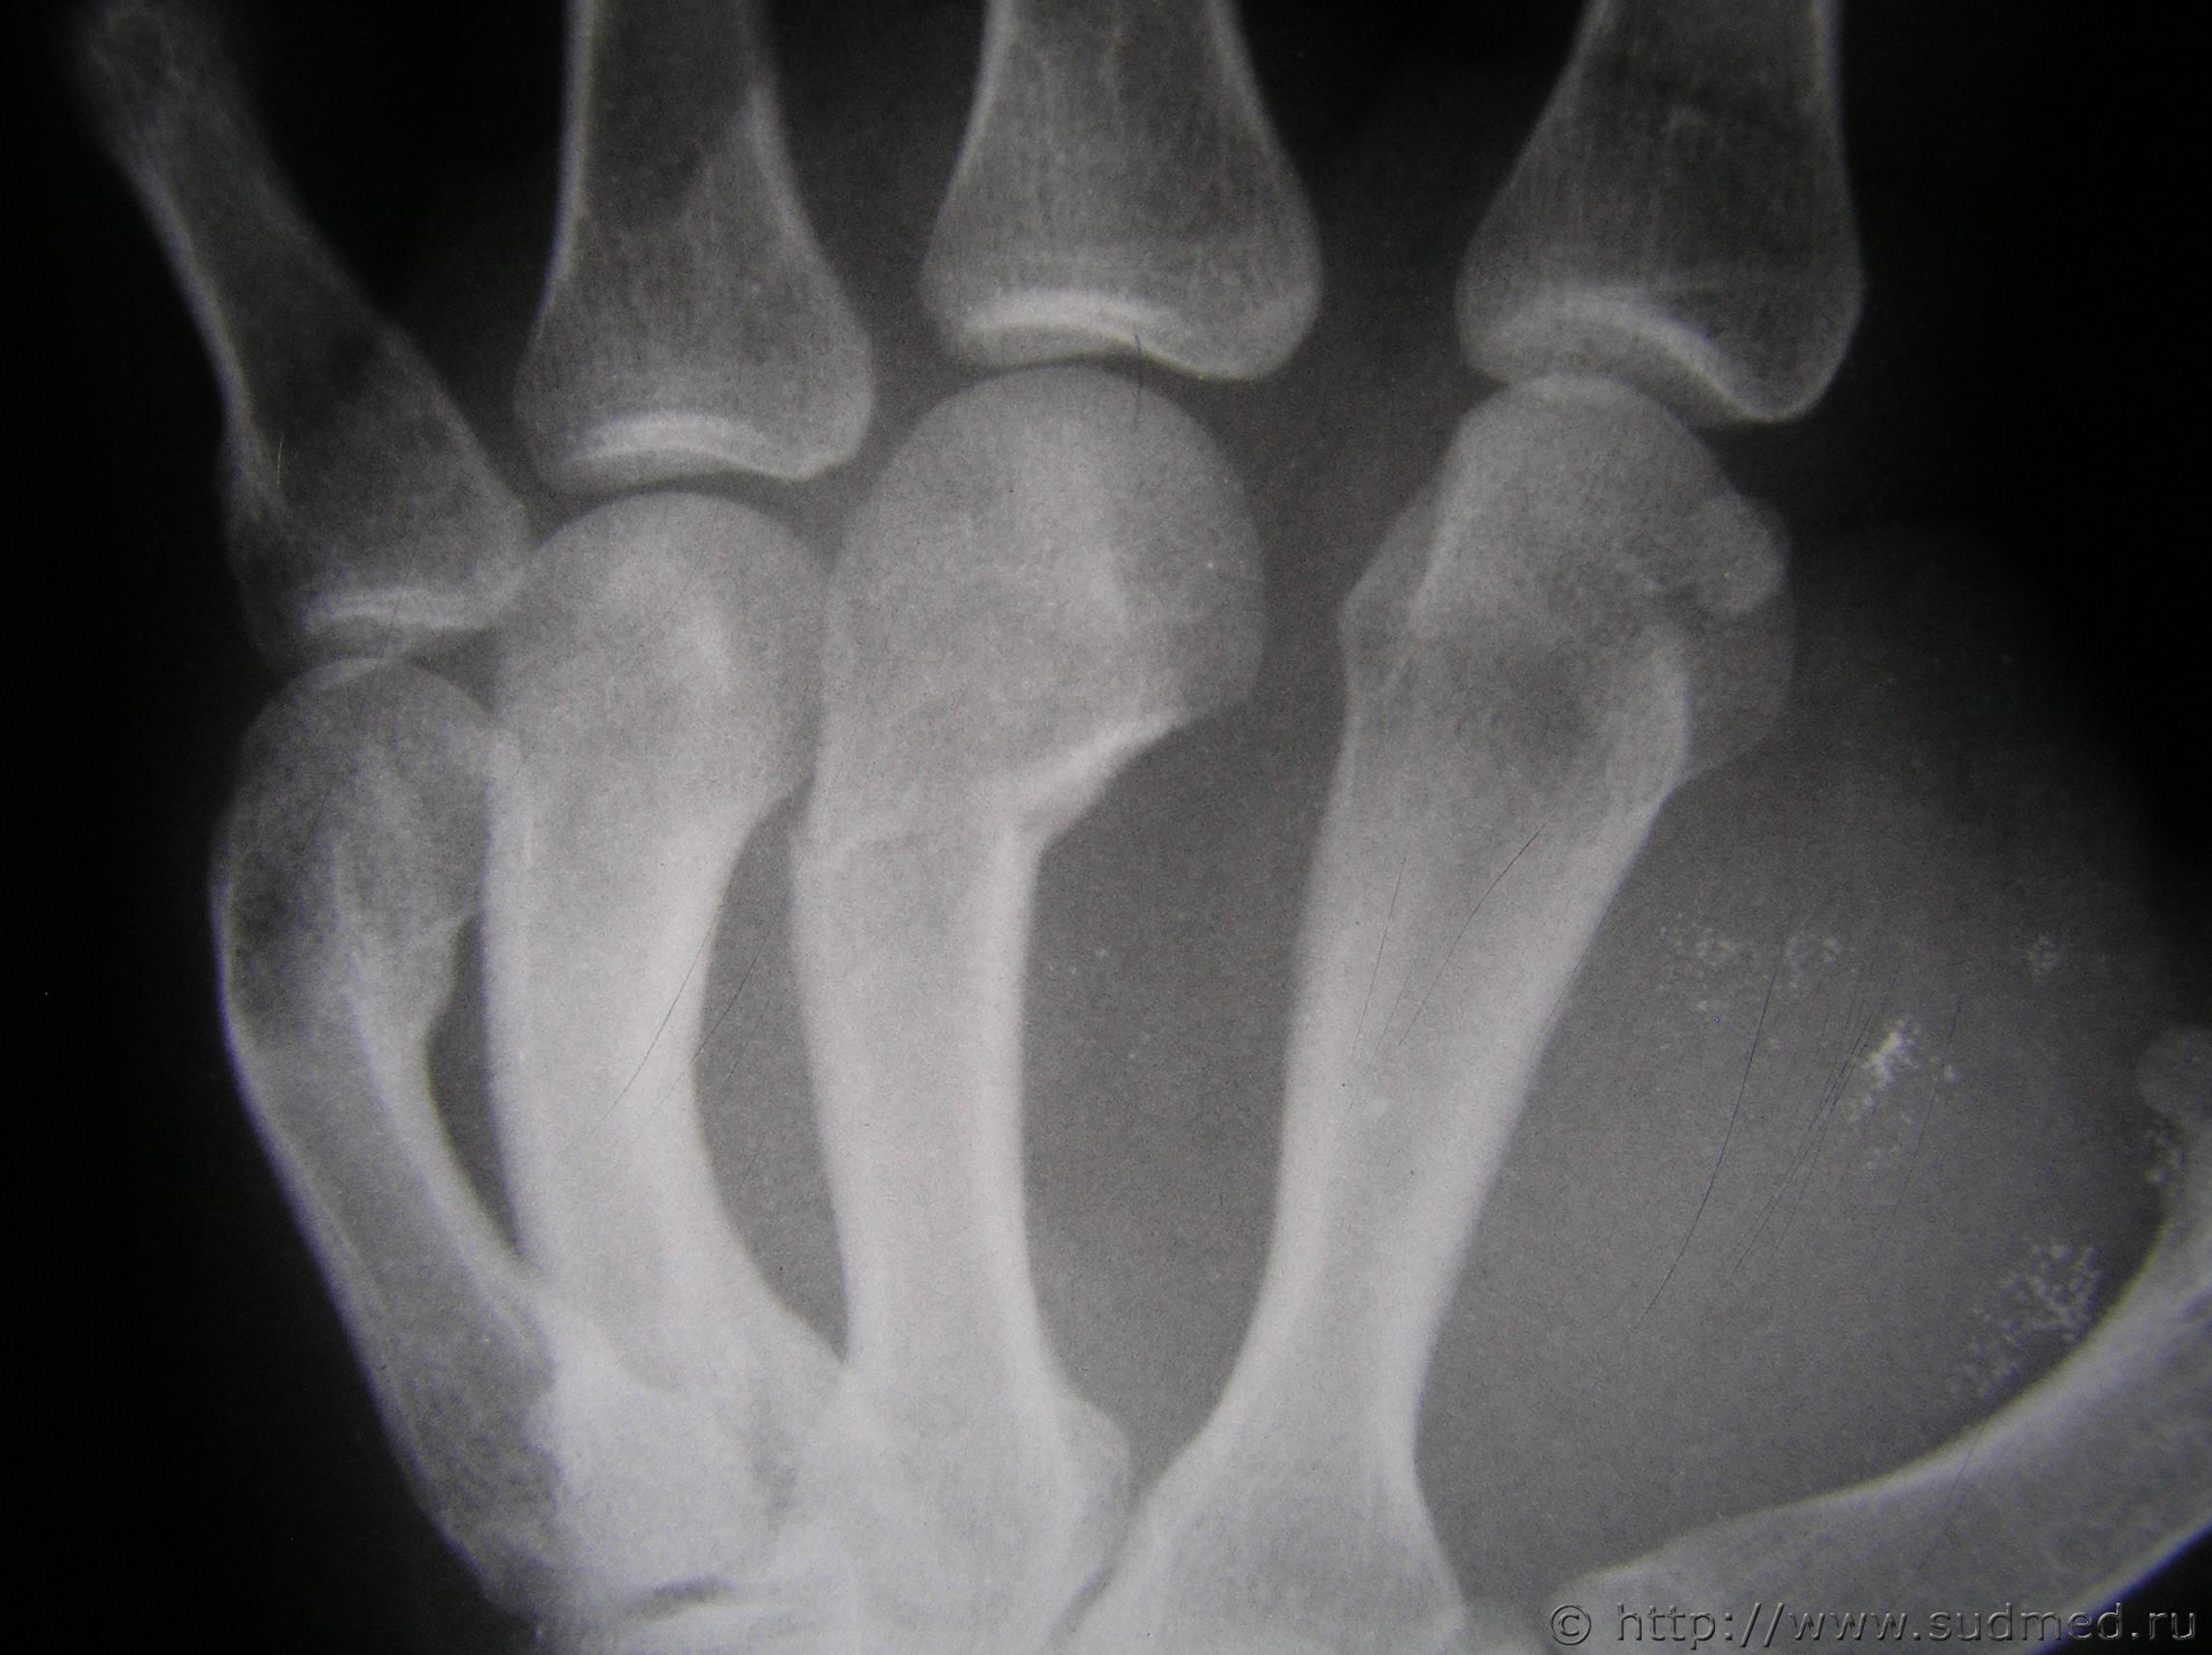

вот рентген. может есть на форуме специалисты которые смогут помочь smile.gif

рентгенография правой кисти

Удар кулаком.

Полностью согласен. удар с упором на пястно-фаланговые суставы

Согласен- нагрузка по оси кости.

боксер не боксер, а наносить удар сломаннной рукой вряд ли кто стал, да еще и при наличии другой, здоровой руки) а тут еще и рентген - осевая нагрузка, так что согласен с остальными - удар рукой

Удар кулаком 100%.Доказано, что при нанесении прямого удара основная нагрузка приходится на II—III пястные кости.+нагрузка по оси.